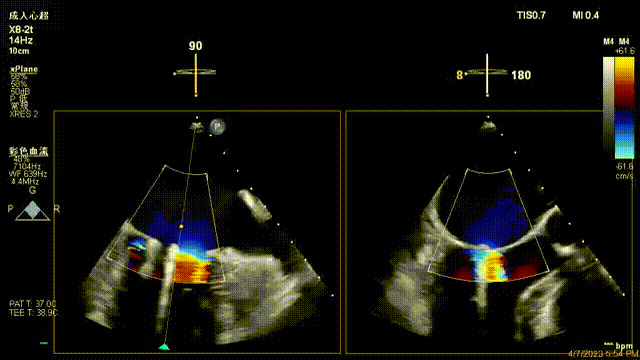

術后超聲顯示二尖瓣反流消失,瓣膜夾穩定

接受治療的是一例器質性重度二尖瓣反流(DMR)患者,主訴“反復活動后胸悶,氣促3年余”。術前超聲顯示,雙房增大,二尖瓣脫垂伴重度反流,輕度三尖瓣反流,輕度肺高壓,升主動脈增寬。手術經股靜脈-房間隔入路,采用全身麻醉插管,在TEE和DSA引導下完成房間隔穿刺。置入JensClip瓣膜夾系統后,在左房調整瓣膜夾的位置和軸向,后進入左室,在TEE引導下捕捉二尖瓣前后瓣葉,并關閉瓣膜夾。經TEE反復確認手術效果后最終鎖定并釋放瓣膜夾。術后即刻超聲顯示瓣膜夾位置穩定,功能良好,術前二尖瓣反流4+,術后0反流,肺靜脈逆流和左房壓都顯著好轉,手術圓滿成功(以上數據都來源于醫院的臨床記錄)。術后患者狀態良好,目前已安排出院。